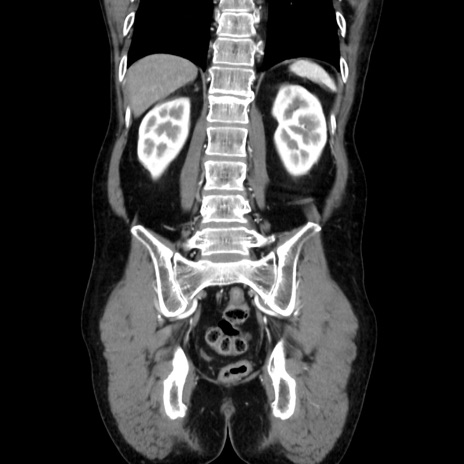

横断像

【症例】40歳代 男性

【主訴】腹痛

【現病歴】4時間ほど前に電車に乗車中に臍部上より腹痛出現。徐々に増悪し起立困難となり、救急外来受診。生ものは数日食べていない。今朝お雑煮を食べた。

【身体所見】BT 36.8℃、BP 117/84mmHg、HR 91/min、SpO2 97%、苦悶様、腹部:臍上部広範囲圧痛あり、反跳痛±

【データ】WBC 8100、CRP 0.03